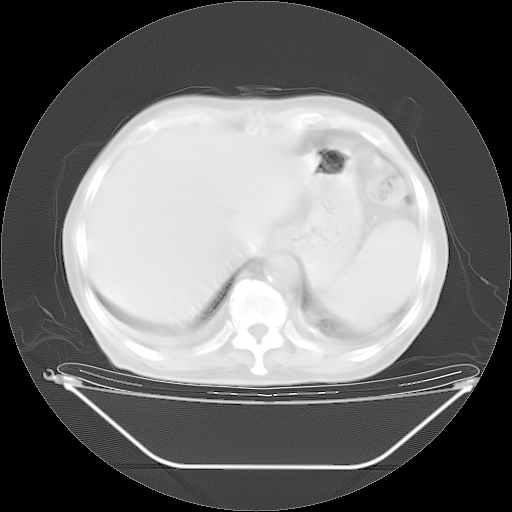

今天复查肺部CT,发现双肺广泛磨玻璃样改变。所以我把3月19日和5月9日相隔50天的肺部CT上传。请大家会诊。

2009年3月19日肺部CT片。

2009年3月19日肺部CT